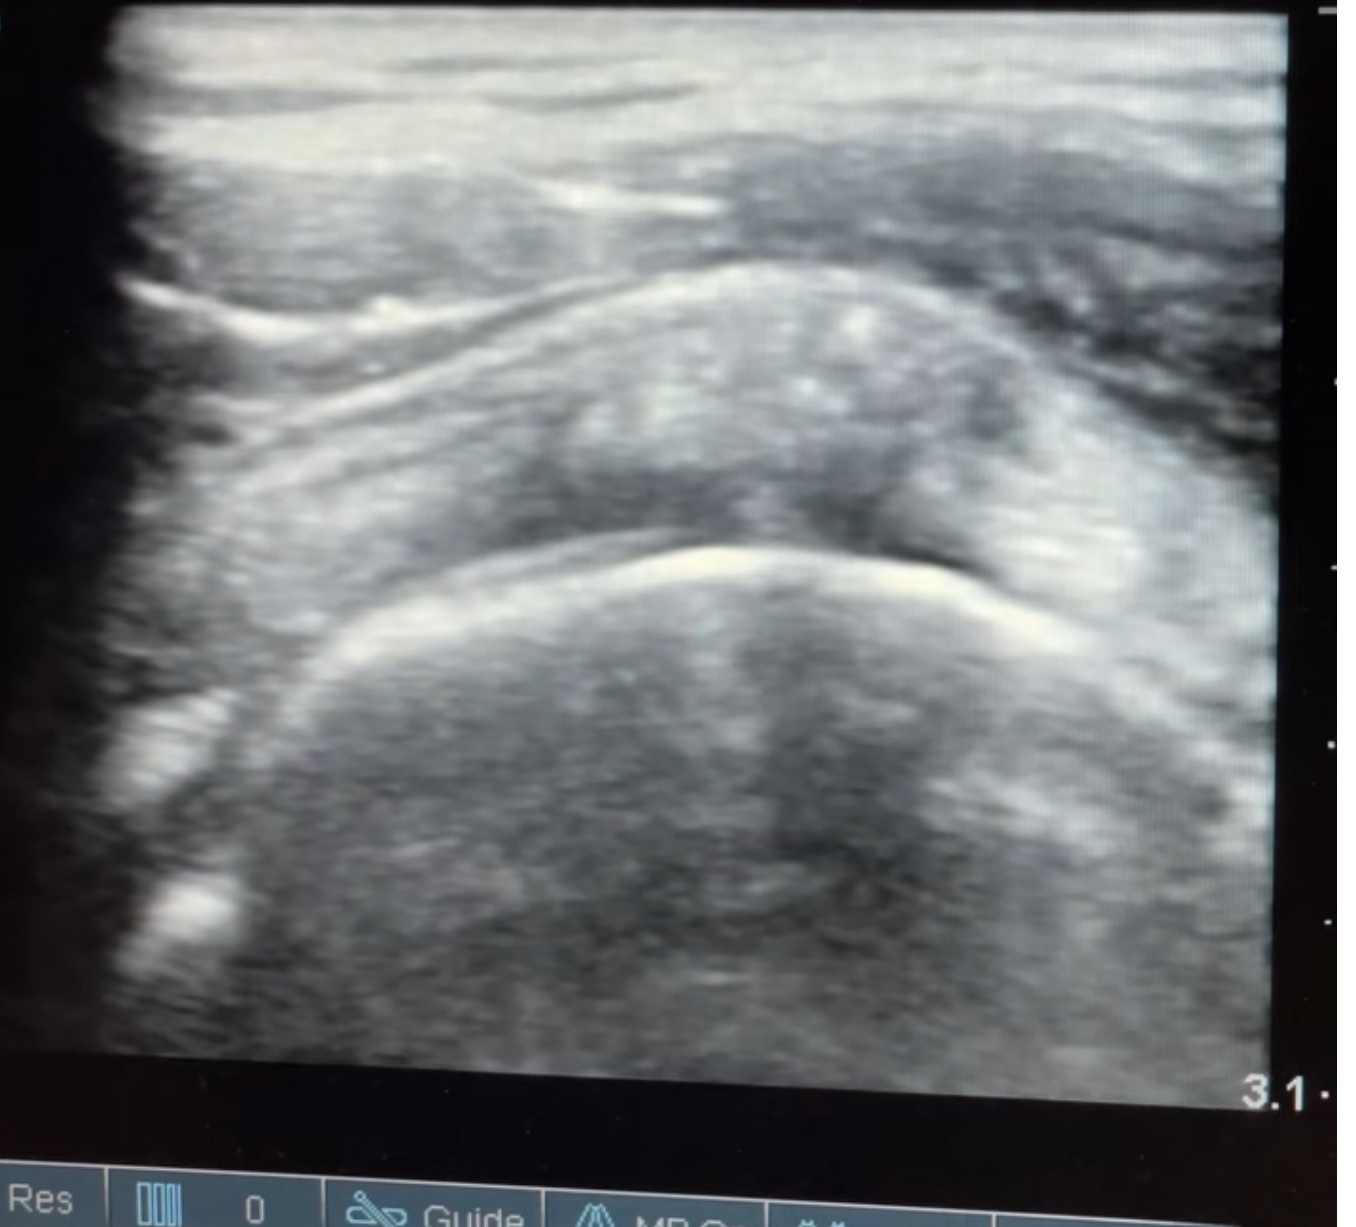

5. มีเสียง “กร๊อบ” หรือ “กึ๊ก” ในไหล่ขณะเคลื่อนไหว

หากคุณได้ยินเสียงกร๊อบหรือกึ๊กขณะเคลื่อนไหวไหล่ และรู้สึกเจ็บหลังจากนั้น อาจเป็นสัญญาณของ การบาดเจ็บในข้อไหล่หรือกระดูก ซึ่งจำเป็นต้องตรวจเพิ่มเติม เช่น การตรวจด้วย Ultrasound หรือ MRI เพื่อดูว่าเกิดความเสียหายที่จุดใด